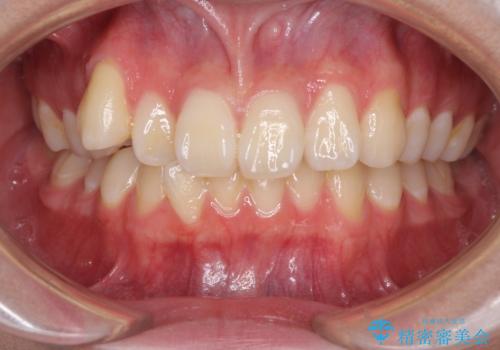

- 八重歯を気にして来院された高校生の患者様です。

ボディーコンタクトの激しい部活動を行っているため、補助装置とインビザラインを用いて、部活動を継続しながら治療を行うこととしました。

八重歯を効率よく改善するため、補助装置を使用して上顎の奥歯を後方に移動させました。

部活動をしながらでしたが、マウスピースをしっかりと装着してくださったので、1年半程度で終了することができました。